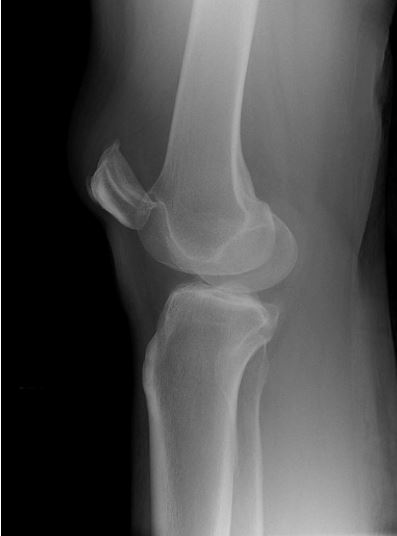

What’s the Diagnosis? Gepost op 12 maart 2020 door netwerkvsseh What’s the Diagnosis? By Dr. Erica Schramm @emdaily.cooperhealth.org Dit delen: Delen op X (Opent in een nieuw venster) X Share op Facebook (Opent in een nieuw venster) Facebook Delen op LinkedIn (Opent in een nieuw venster) LinkedIn E-mail een link naar een vriend (Opent in een nieuw venster) E-mail Afdrukken (Opent in een nieuw venster) Print Vind-ik-leuk Aan het laden... Gerelateerd